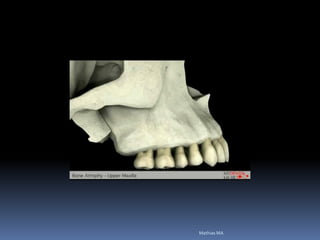

Exames Imaginológicos

Radiografias periapicais, telerradiografias e

panorâmicas;

Tomografias computadorizadas

Softwares de imagens 3D

Atrofias óssea

Redução das dimensões ósseas ideais

•Estabilidade implantar

•Estética

•Função